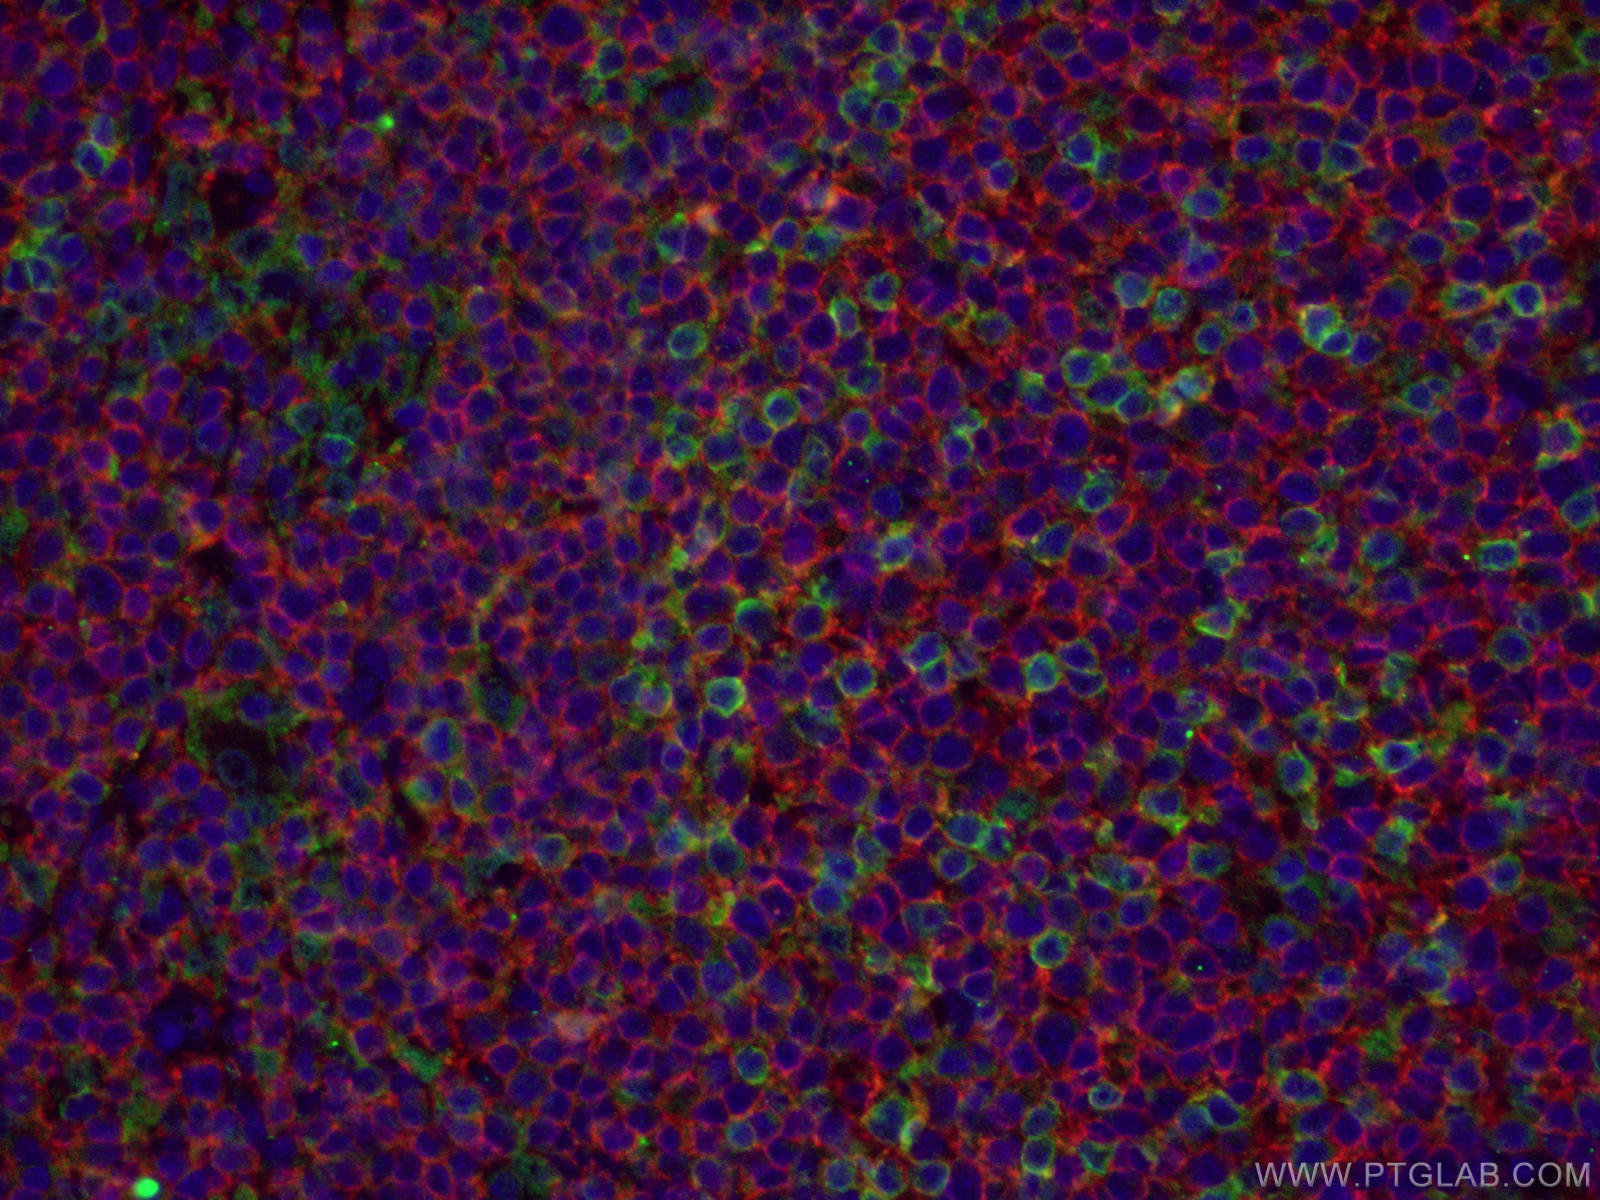

| Positive IF-P detected in | human tonsillitis tissue, Raji cells |

24828-1-AP targets CD20 in WB, IHC, IF/ICC, IF-P, IP, ELISA applications and shows reactivity with human samples.

CD20 is a 33-37 kDa transmembrane phosphoprotein. CD20 is a B-lymphocyte surface molecule that is widely expressed during B-cell ontogeny, from early pre-B-cell developmental stages until final differentiation into plasma cells. CD20 functions as calcium-permeable cation channel. It is involved in the regulation of B-cell activation and proliferation. CD20 serves as a useful target for antibody-mediated therapeutic depletion of B-cells.